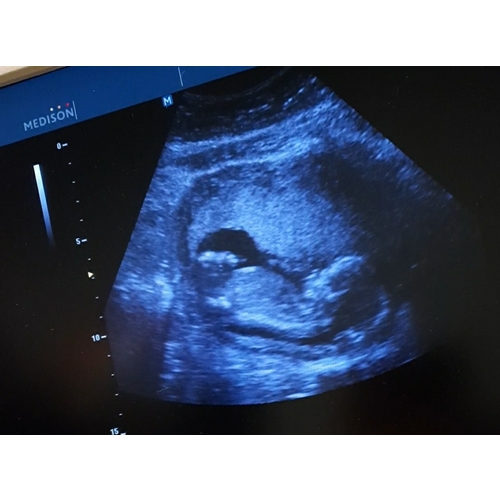

15 weken.. kan iemand hier iets op zien?

Geen sprake van nub meer bij 15wmaar ik ga voor 馃挆